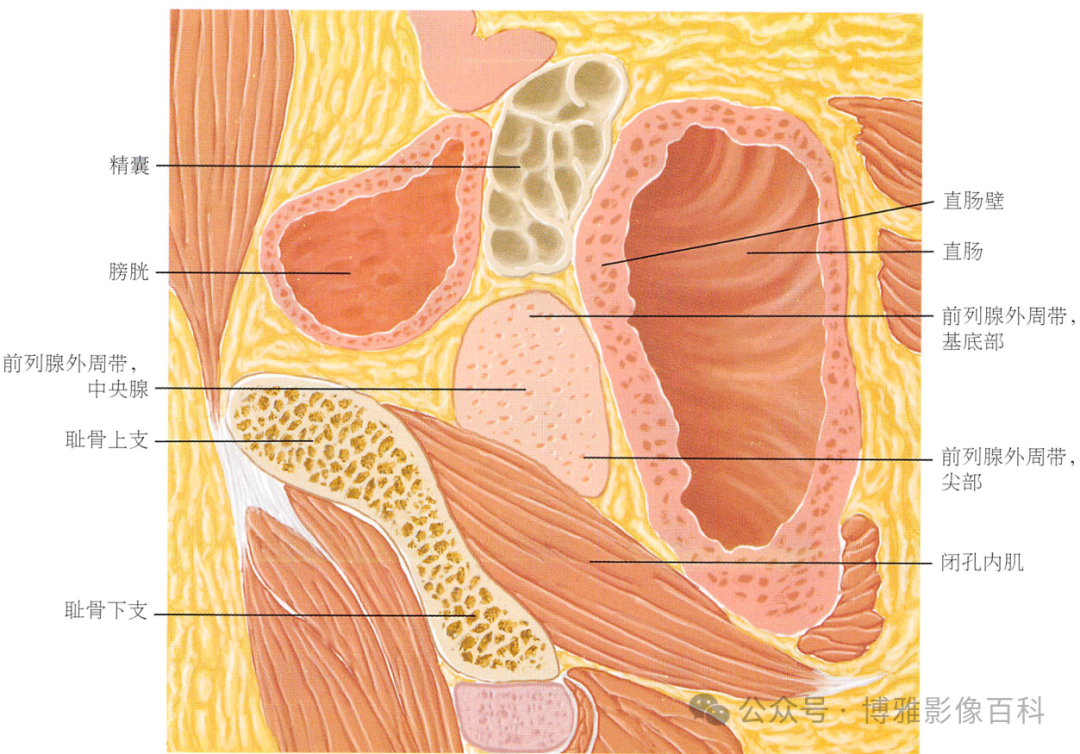

解剖学

前列腺分区解剖学

MR 解剖学